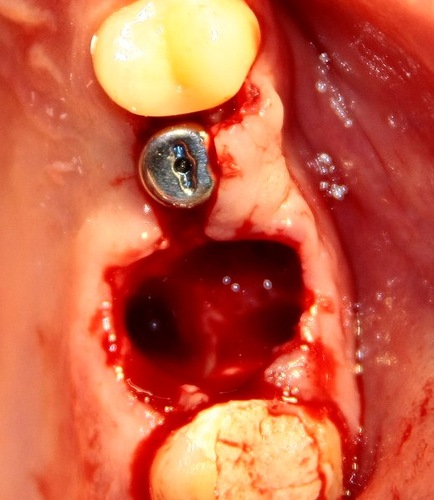

Если зуб ломается, если не удается его вытащить целиком — не нужно этого делать. С помощью бормашины можно поделить зуб на несколько частей — и удалить его по частям. Это намного проще.

Сломался мелкий корешок где-то в глубине лунки? Промойте лунку физраствором, дистиллированной водой, раствором хлоргексидина — и у Вас будет нормальный обзор. Ни в коем случае нельзя работать вслепую.

Еще забудьте про молоток и долото. У вас есть бормашина — пользуйтесь ей. Да, это не так эффектно выглядит, как при использовании молотка и долота, но зато избежите осложений и негатива со стороны пациента.![0_e8c0a_36b90d0a_L[1]](http://2026.implant-in.com/wp-content/uploads/2013/09/0_e8c0a_36b90d0a_L1-150x150.jpg)

Ну ладно, удалили зуб. Что делать с лункой?